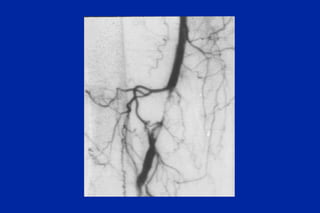

Este documento resume los principales tipos y técnicas de angiografía. Describe brevemente la angiografía, arteriografía, flebografía y linfografía, así como las técnicas de contraste y materiales utilizados. También explica los principales accesos vasculares, la técnica de Seldinger, la angiografía por sustracción digital y algunas técnicas endovasculares comunes.